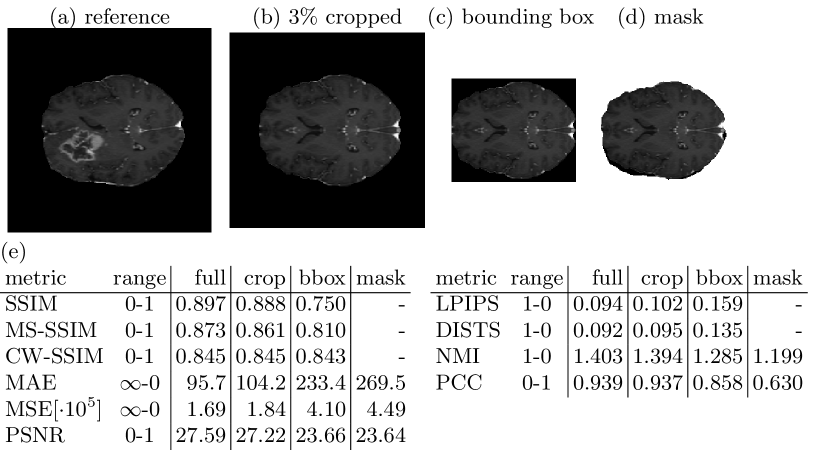

3.3 Pitfall 3: Background, Foreground and Region of Interest Similarity

Medical images are often acquired to detect a pathological condition in a very specific location in the human body. Even though the field of view can be narrowed, medical images often picture neighboring structures and a large fraction of background, that are not of interest for diagnosis. Similarity of medical images is especially relevant for a limited region of interest, i.e. a possible lesion or tumor, a specific organ, bone, muscle or tendon. Pictures of brain tumors are perceived more similar, if they show the same type of tumor at the same location, rather than the same texture of healthy brain tissue or even the same background intensity. Therefore, it is important to be able to mask out rather irrelevant parts of an image and to evaluate specified regions of interest separately. Fig. 3 shows similarity metric scores for increasingly cropped brain images, where the test image consists of the upper hemisphere of the brain in the reference image and the lower half of the image is replaced by a mirror of the upper hemisphere. In most cases of the BraSyn Dataset this leads to either two or no tumors in the test image opposed to exactly one tumor in the reference image. However, when background composes a large part of the image to be evaluated, similarity metric scores appear very high. With decreasing background the similarity metric scores also noticeably decrease.